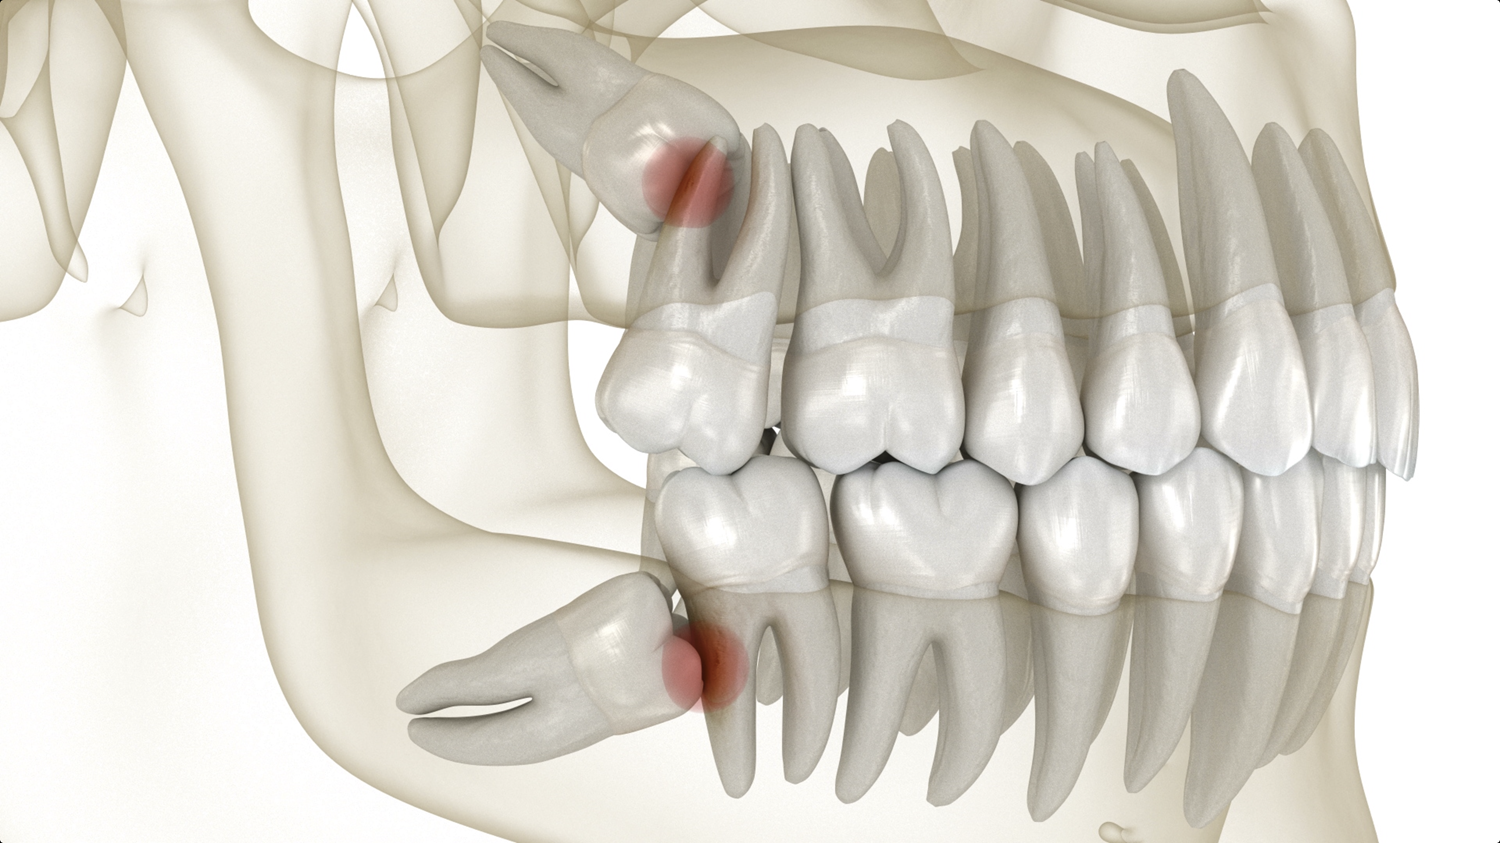

There are many reasons why wisdom teeth removal may be necessary. This includes wisdom teeth growing in at the wrong angle. They can grow sideways, partially erupt, or even become trapped underneath the gum and bone. Impacted wisdom teeth can take many positions in the bone as they try to find a pathway to successfully erupt. All of these reasons make wisdom teeth removal necessary to preserve your oral health.

Wisdom teeth can cause pain and discomfort. They have no limitations in how they erupt, often growing sideways or putting uncomfortable pressure on your other teeth. Wisdom teeth removal will relieve the pain and release your teeth from the pressure.

Wisdom teeth often have to be extracted to ensure the rest of your teeth stay healthy. Most wisdom teeth erupt misaligned, which can cause tooth crowding and disruption in your teeth and gums. This is not only painful but can make oral hygiene more difficult. Another common reason for wisdom teeth extraction is a partial eruption. This encourages bacteria to accumulate in the pockets of your gums, putting you at risk for gum disease, infection, and tooth decay. That being said, sometimes wisdom teeth don’t always need to be removed. If your wisdom teeth erupt properly aligned and don’t impact your other teeth, your doctor may not recommend extraction. But generally, wisdom teeth need to be removed to preserve a healthy smile.